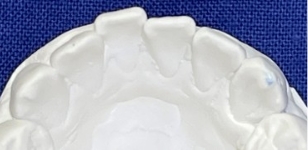

観察方法はPARスコアではなく、もう少しダイレクトな評価になるリトル教授らの方法を使いました。つまり右図のように、後戻りが一番現れやすいと言われている下の前歯において、歯と歯の接触点間の距離をmm単位でデジタル写真上で計測し、それらの合計のミリ数を「指数」とするものです。歯並びが綺麗であれば“0”に近い数字になり、数字が大きいと悪い歯並びを意味します。この写真の歯と歯の接触点間の距離の合計は9.3mmでしたから、指数は9.3になります。